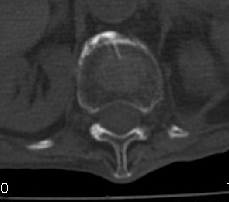

男:89岁因外伤后2天行ct检查。请各位战友讨论图中所指是否是骨折和形成该影像的原因(扫描层面位于椎体中份)。

椎体前缘双边征,其后椎体内密度增高均提示压缩性骨折

老年性骨质疏松,椎体前缘出现双边征支持压缩骨折。椎体骨质稀疏,似有破坏,警惕溶骨性骨转移。

椎体前缘呈双边征 考虑 压缩性骨折,椎体退行性病变。

我的报告1:腰椎骨质退行性改变。

2:t12改变考虑压缩骨折?请结合临床。